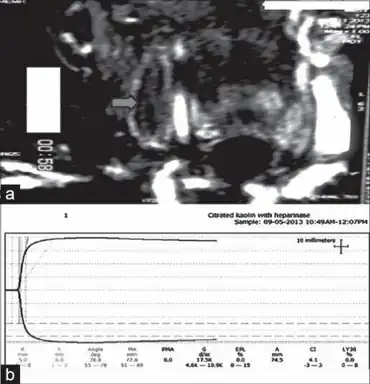

| An ultrasound image demonstrating a blood clot in the left common femoral vein. | |

Recurrent miscarriage is an indication for thrombophilia screening, particularly antiphospholipid antibodies (anti-cardiolipin IgG and IgM, as well as lupus anticoagulant), factor V Leiden and prothrombin mutation, activated protein C resistance and a general assessment of coagulation through an investigation known as thromboelastography.[10]